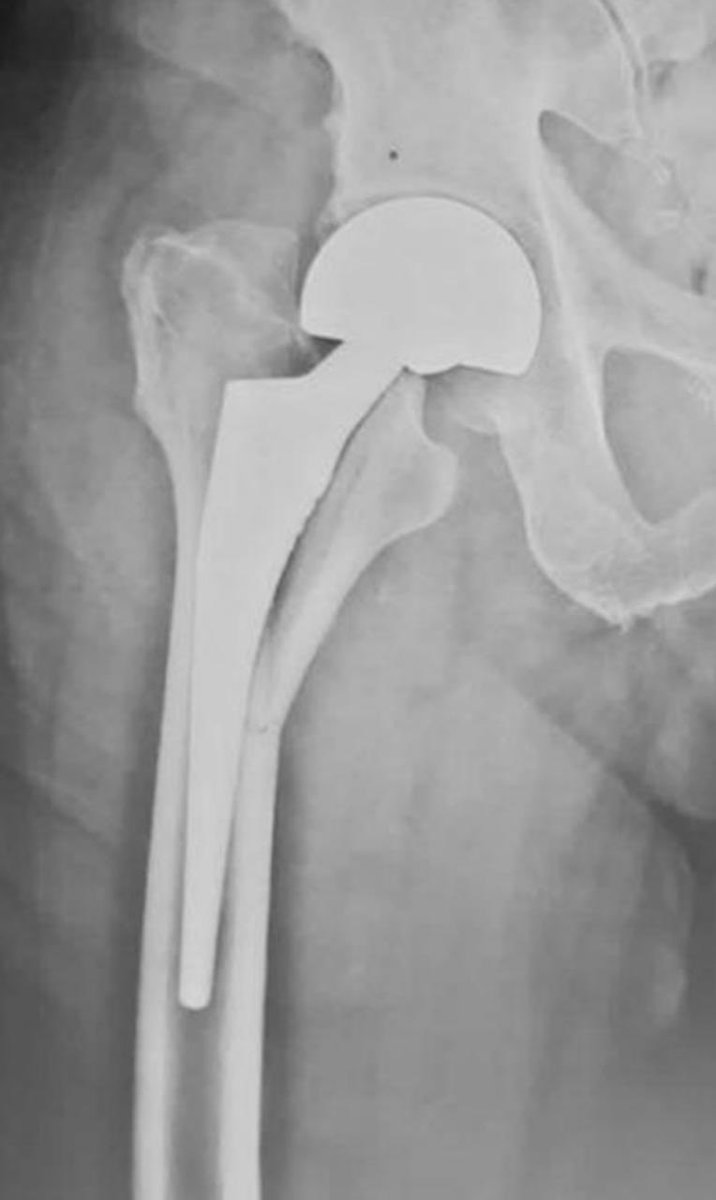

Dogs, orthopaedic surgery, science, and Oxford commas.